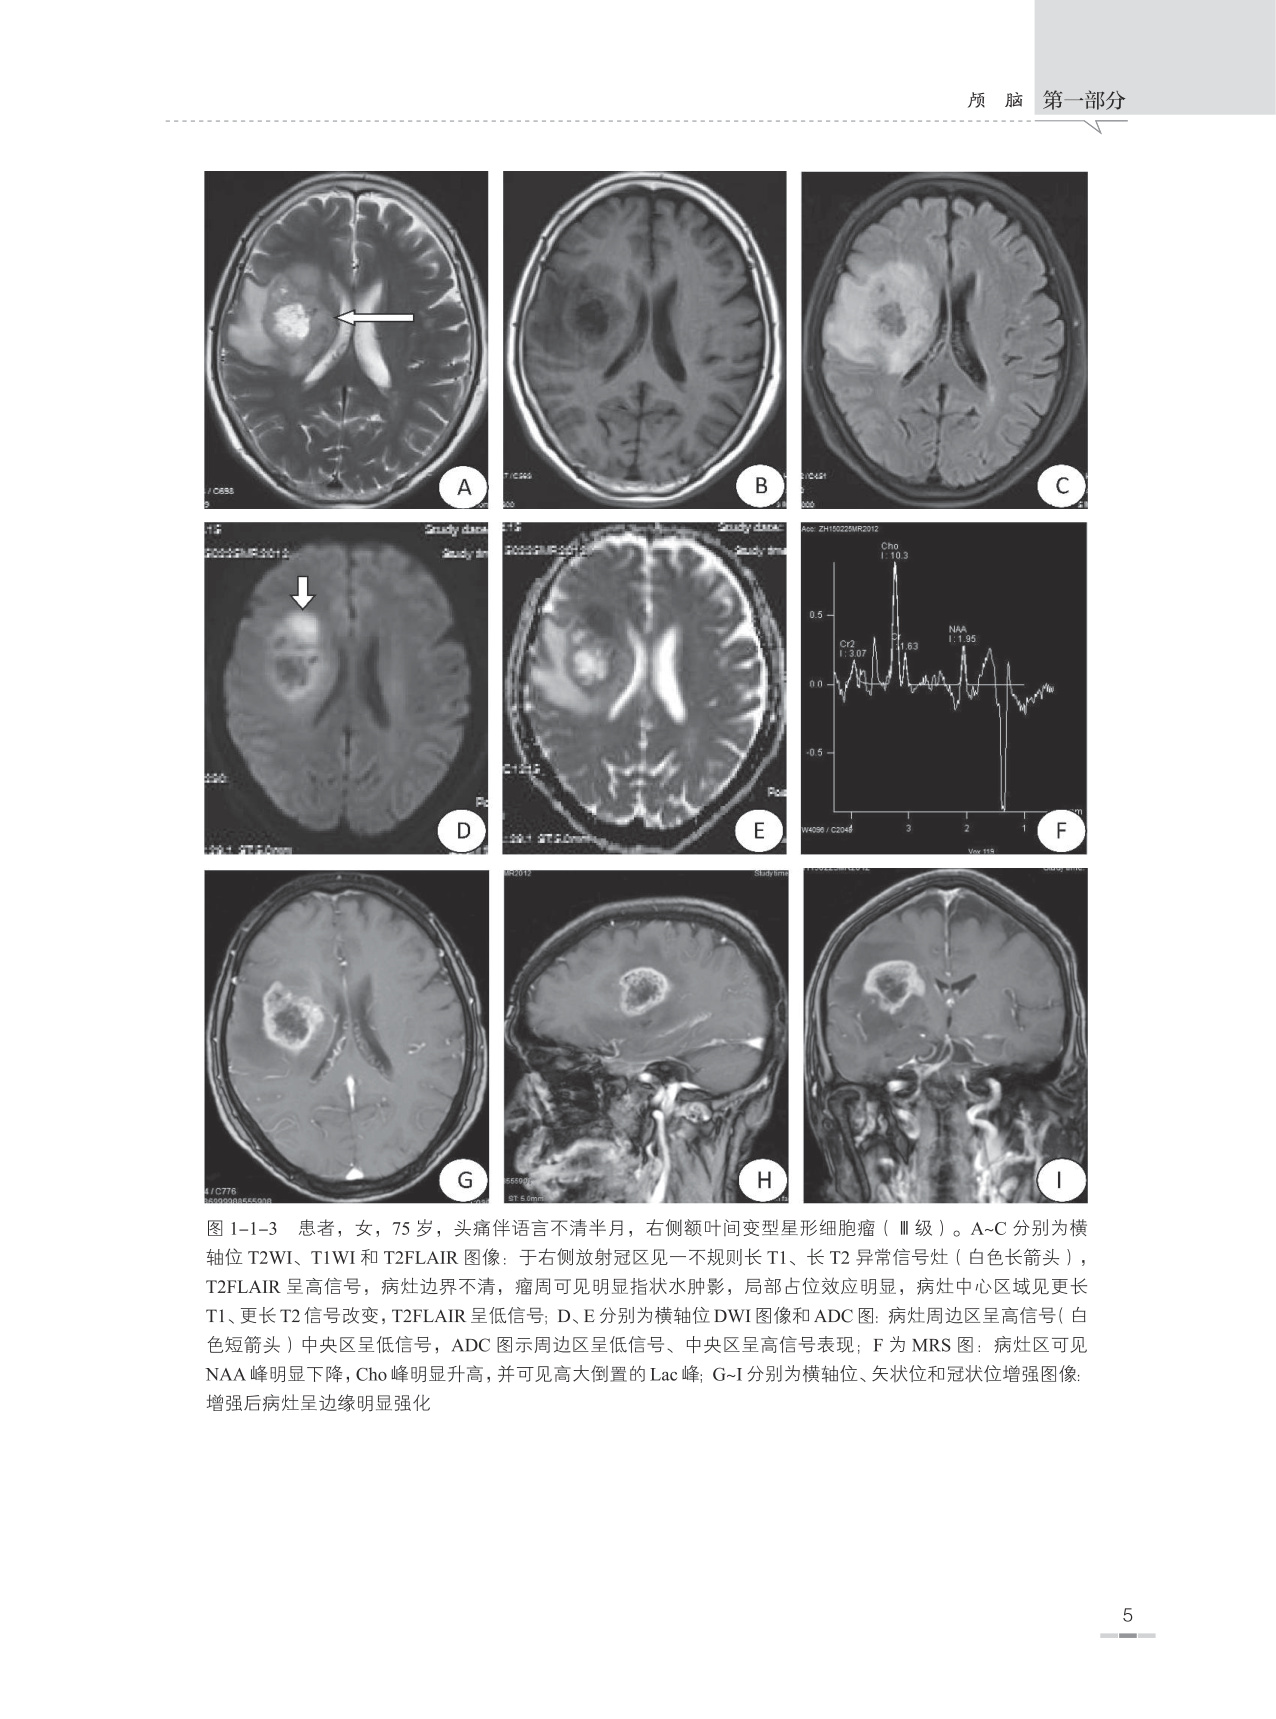

本书是根据作者本人多年临床工作经验并参考大量中外文献资料编写而成的,书内附图均为作者在40余年日常临床医学影像诊断工作中所收集留存的典型病例,书中对每一种疾病所涉及的内容包括疾病概述、流行病学、治疗与预后、病因、发病机制、病理、临床表现、影像学表现、典型病例图像、鉴别诊断及主要参考文献,以便读者能够全面理解和掌握疾病的临床及影像学表现特征。另外在每一种疾病论述开始之前附有本疾病的主要表现特征和诊断要点,以便读者能够快速掌握疾病的重点。

本书主要面向医学影像学诊断医师和医学影像学专业学生,并力求为各级医院神经内科、神经外科、急诊科、ICU、肿瘤科、脊柱外科、康复科、介入科、放疗科、病理科等相关科室以及全科医师提供神经系统疾病的影像学诊断信息,让广大的临床医师更好地了解医学影像学诊断技能在中